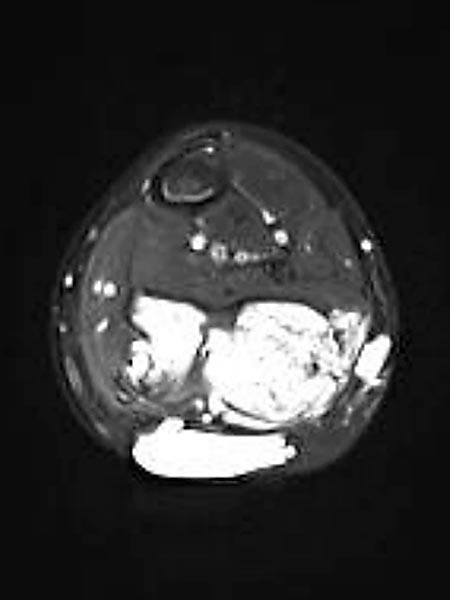

Der zweite, deutlich kleinere, Wadenmuskel (Musculus soleus) ist in der transversalen, T2-gewichteten, fettunterdrückten MRT nicht betroffen. Er muss postoperativ die Kraft übernehmen. Zusätzlich finden sich epifaszial lymphatische Malformationsanteile.